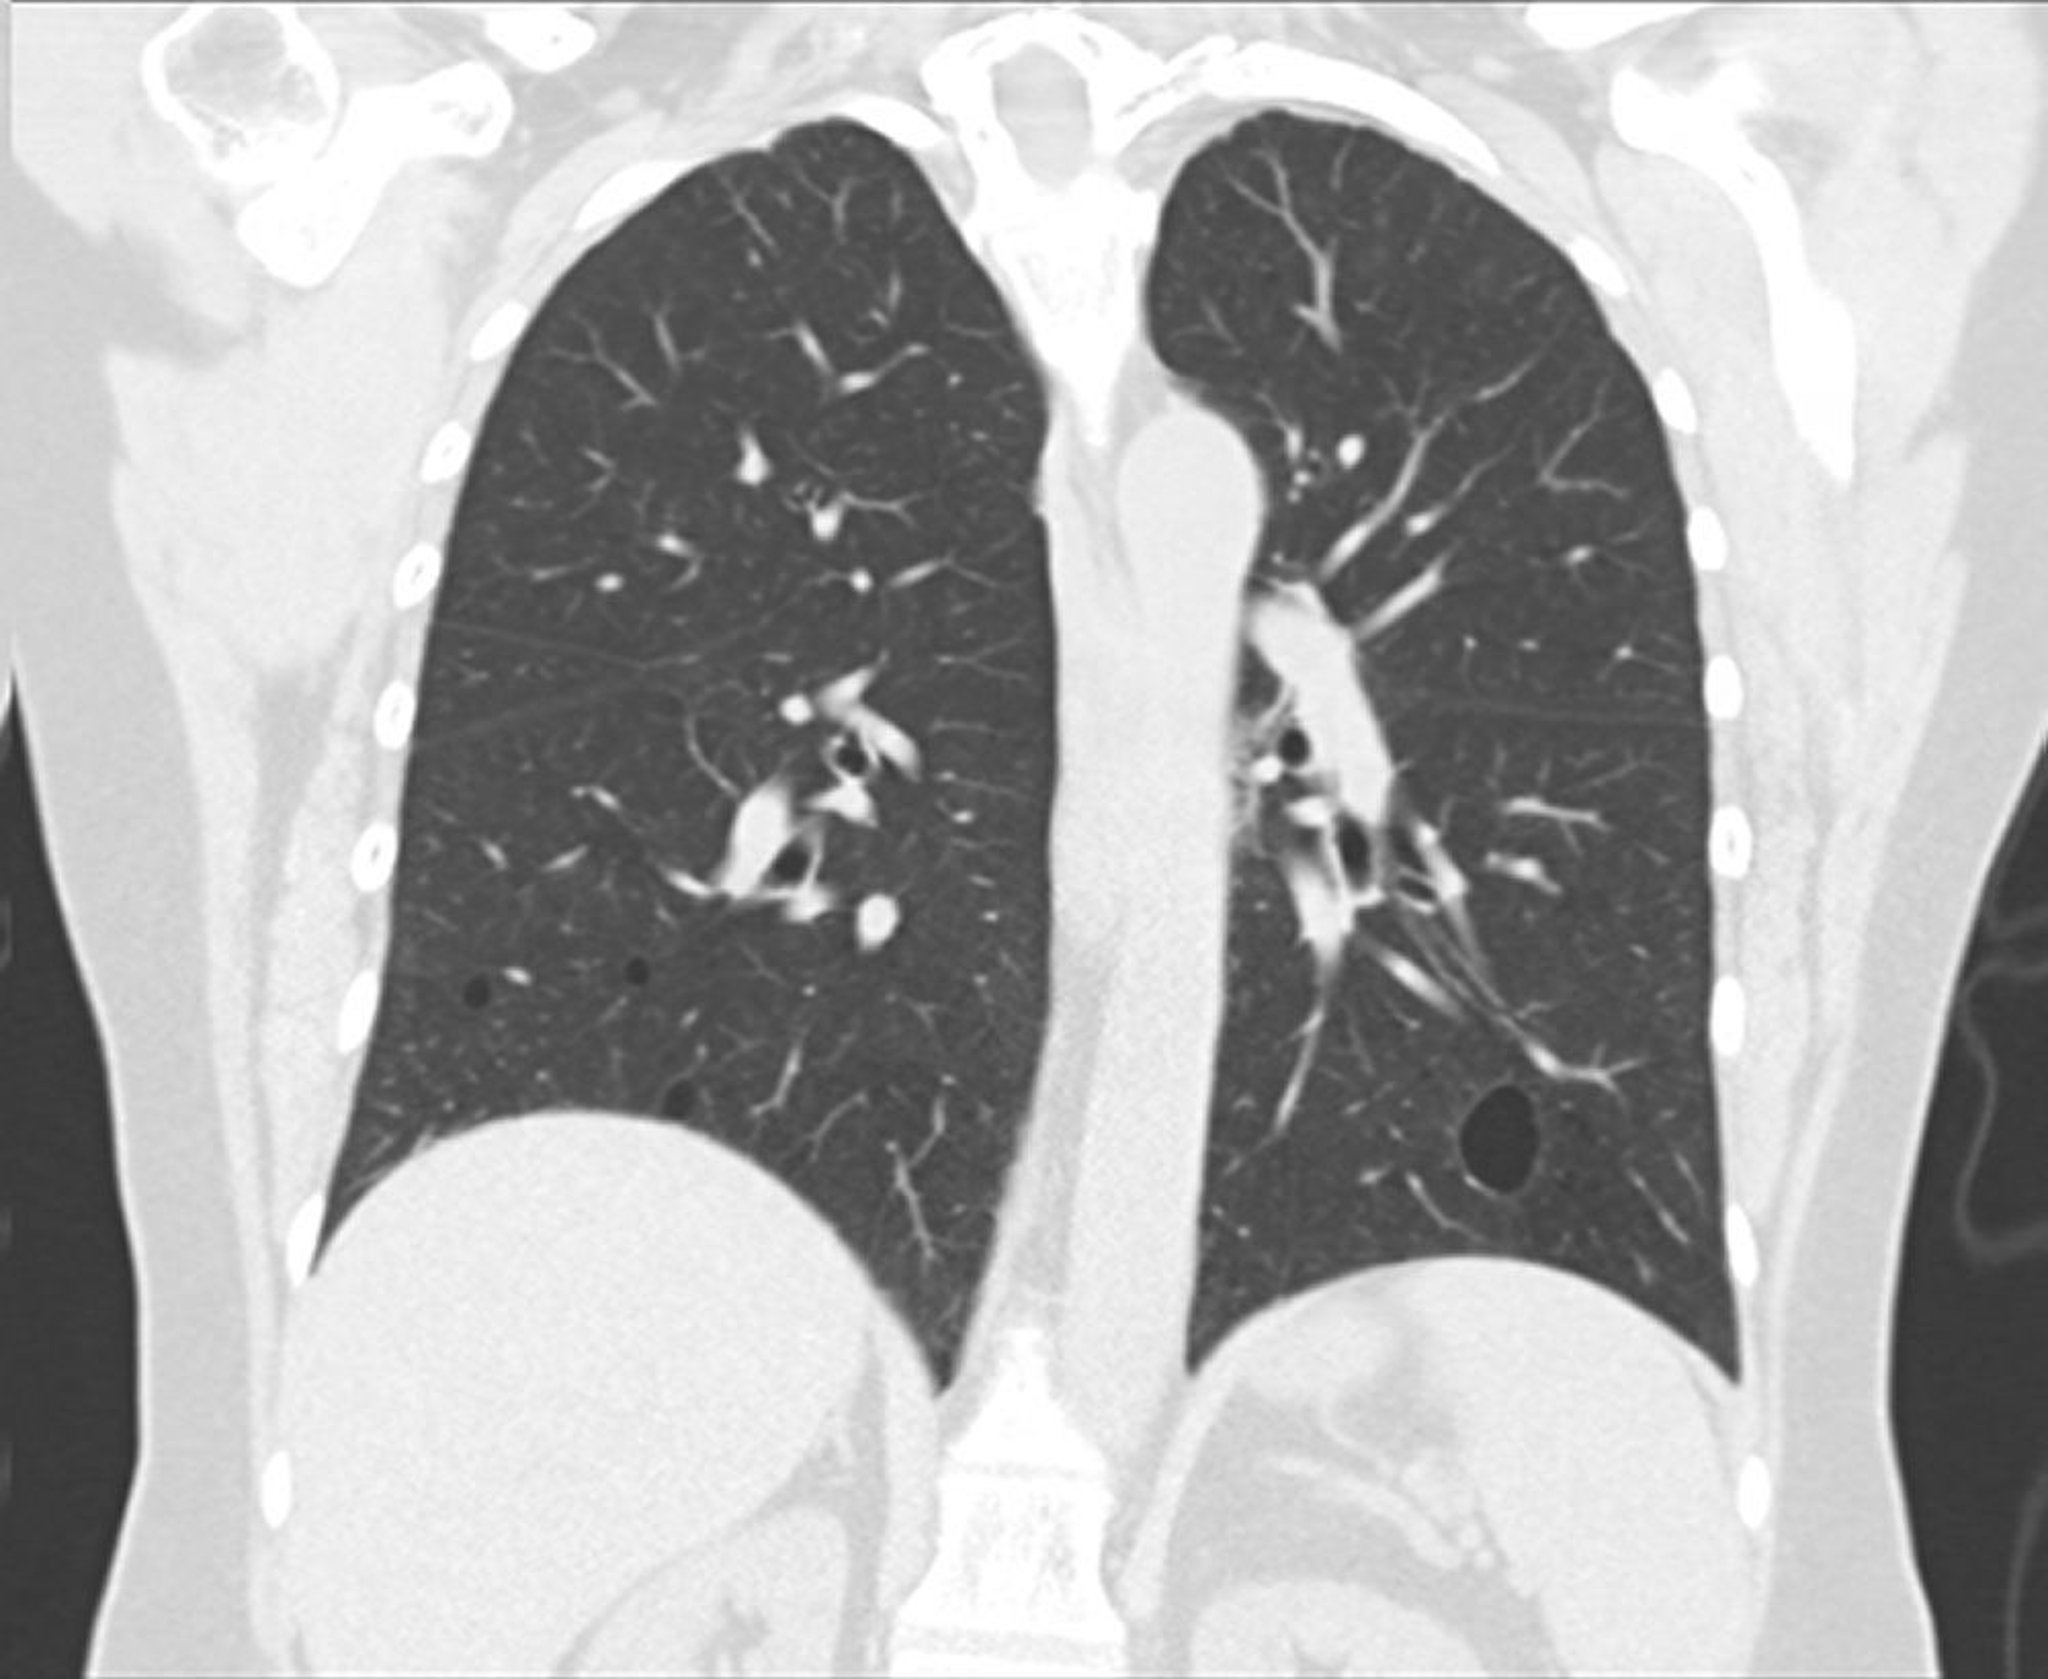

Viêm phổi kẽ lympho bào

Hình ảnh này cho thấy bệnh viêm phổi kẽ lympho bào thứ phát do hội chứng Sjögren. Có thể nhìn thấy các nang được bọc kín ở các thùy dưới hai bên trên phần chụp CT hướng đứng ngang.

Hình ảnh này do bác sĩ Tami Bang cung cấp